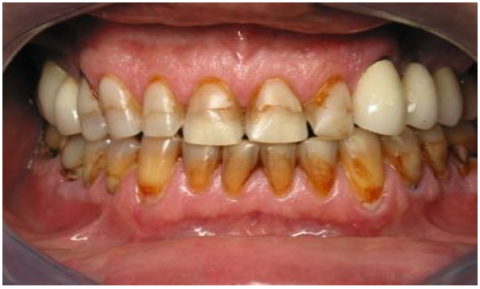

The dataset used in this study consists of 10,573 clinically sourced dental images, including contributions from publicly available repositories such as Kaggle. It provides a comprehensive foundation for training, validating, and testing the dental disease detection system [15]. The images are categorized into five distinct dental conditions: caries (2,382 images), gingivitis (2,349 images), hypodontia (1,251 images), mouth ulcers (2,541 images), and tooth discoloration (2,050 images) (Figure 1).

a

b

c

d

e

Figure 1. Dataset samples. (a) Caries, (b) Gingivitis, (c) Hypodontia, (d) Mouth ulcers, (e) Tooth discoloration